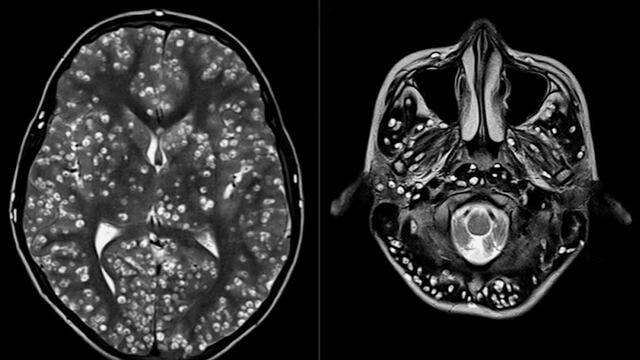

Un joven que tenía el cerebro lleno de larvas perdió la vida a los 18 años, apenas dos semanas después de presentarse en un hospital de Haryana, la India, con fuertes dolores de cabeza, además de convulsiones.

Nada podía evitar que muriera. Padecía 'neurocisticercosis', enfermedad parasitaria causada por huevos microscópicos de una tenia porcina que afectan el tejido muscular y que se propagan al cerebro.

El mayor problema de este padecimiento es que sus víctimas pasan mucho tiempo sin presentar síntomas y en este caso, el joven no se sintió mal hasta que la muerte estaba próxima, cuando su corteza cerebral y el tronco encefálico estaban llenos de larvas, informa New England Journal of Medicine.